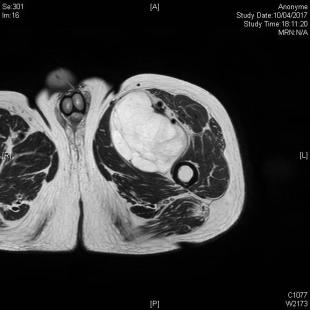

Néanmoins, c’est l’IRM qui est l’examen de référence. Sa version injectée permet de mieux distinguer lipomes, kystes synoviaux, tumeurs à cellules géantes, tumeurs nerveuses ou encore contenant une composante myxoïde (fig. 2 et 3). Mais, dans la majorité des cas, aucun diagnostic de certitude ne peut être obtenu à ce stade et la biopsie sera nécessaire avant d’entreprendre le traitement (fig. 1).